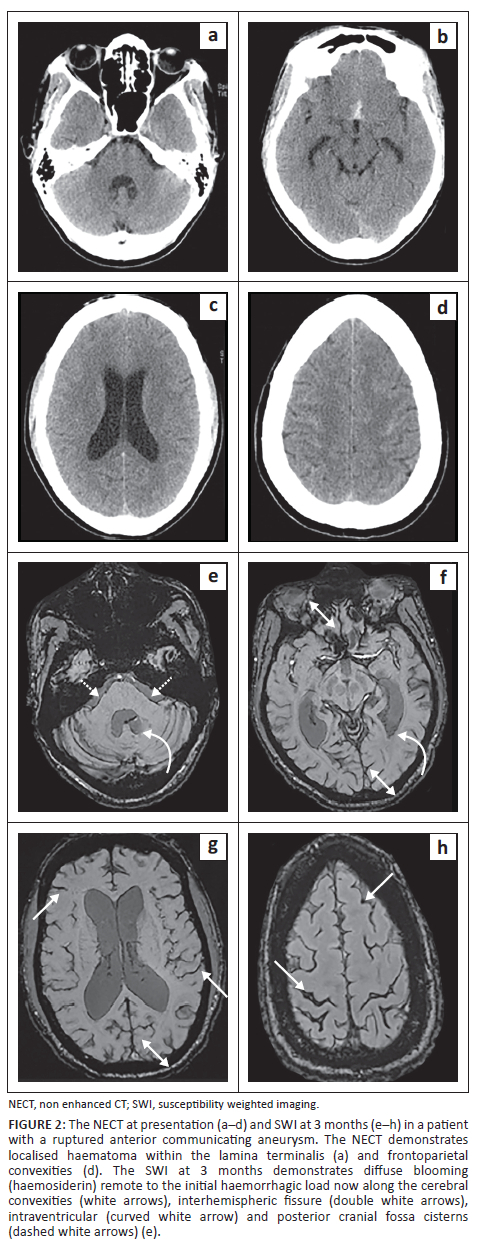

This study demonstrated the ability of SWI to detect ASAH in the chronic phase (> 3 months) after a single aneurysmal haemorrhage: 95.7% (44/46) as depicted in Figure 2. These findings exceeded previous studies utilising T2* in the same setting with rates of only 54.2% - 89.9%.13,14,15,16 This is likely attributable to SWI employing phase differences, which may not necessarily correspond to noticeable T2* effects, as shown in intraparenchymal haematomas demonstrating increased sensitivity of up to 4× in SWI.15

Overall, SWI detected more regions of haemorrhage than the initial CT (as depicted in Figure 2) with a location-based sensitivity of 56% and specificity of 50%. A previous study by Mulé with T2* showed a similar sensitivity of 64% with an improved specificity of 82%.16 The marked difference in specificity was unanticipated and thought to be because of CSF flow dynamics causing haemorrhage to be washed to more regions remote from the site of rupture and hence detected on imaging in the chronic phase.12,13,16

This study showed a sensitivity of 50% in the perimesencephalic cistern, exceeding that of previous studies with T2* of 8%.16 The poor sensitivity in this region was because of regional artefact from the base of skull and high CSF flow displacing any haemorrhage as depicted in Figure 3.12,13,16,17,18

Previous T2* studies in chronic ASAH showed poor sensitivities in the detection of haemorrhage in the ventricular system. Mulé et al. demonstrated a sensitivity of 10%.16 This was thought to be related to high CSF flow velocities in these locations, preventing adequate time for haemosiderosis.12,13,16 The current study contradicted this with increased sensitivity of 62.5% for haemosiderin, even exceeding regions seen on the initial NECT as depicted in Figure 4. These areas of haemosiderin identified on SWI were located in the dependent regions of the ventricular system (occipital horns of the lateral ventricles and dependent lateral recesses of the 4th ventricle).